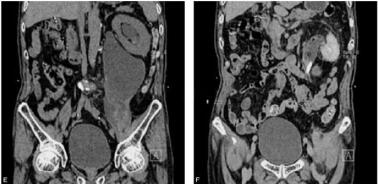

患者男,80岁,以“左腰疼痛20天”为主诉门诊检查(图1)。

图1 左肾后方见不规则囊性密度病灶,壁薄,其内呈液体密度,囊壁明显强化,内部未见强化,左肾后间隙延伸至髂腰肌下缘水平,其前上缘局部可见尖角状改变,与相邻左输尿管关系密切,邻近腰大肌受压萎缩,左髂肌受压。右输尿管未见异常。F图示左输尿管上段内见类椭圆形高密度结石影,其近端输尿管及左肾盂轻度扩张,左肾增大前移,肾周脂肪间隙见少许渗出絮状影